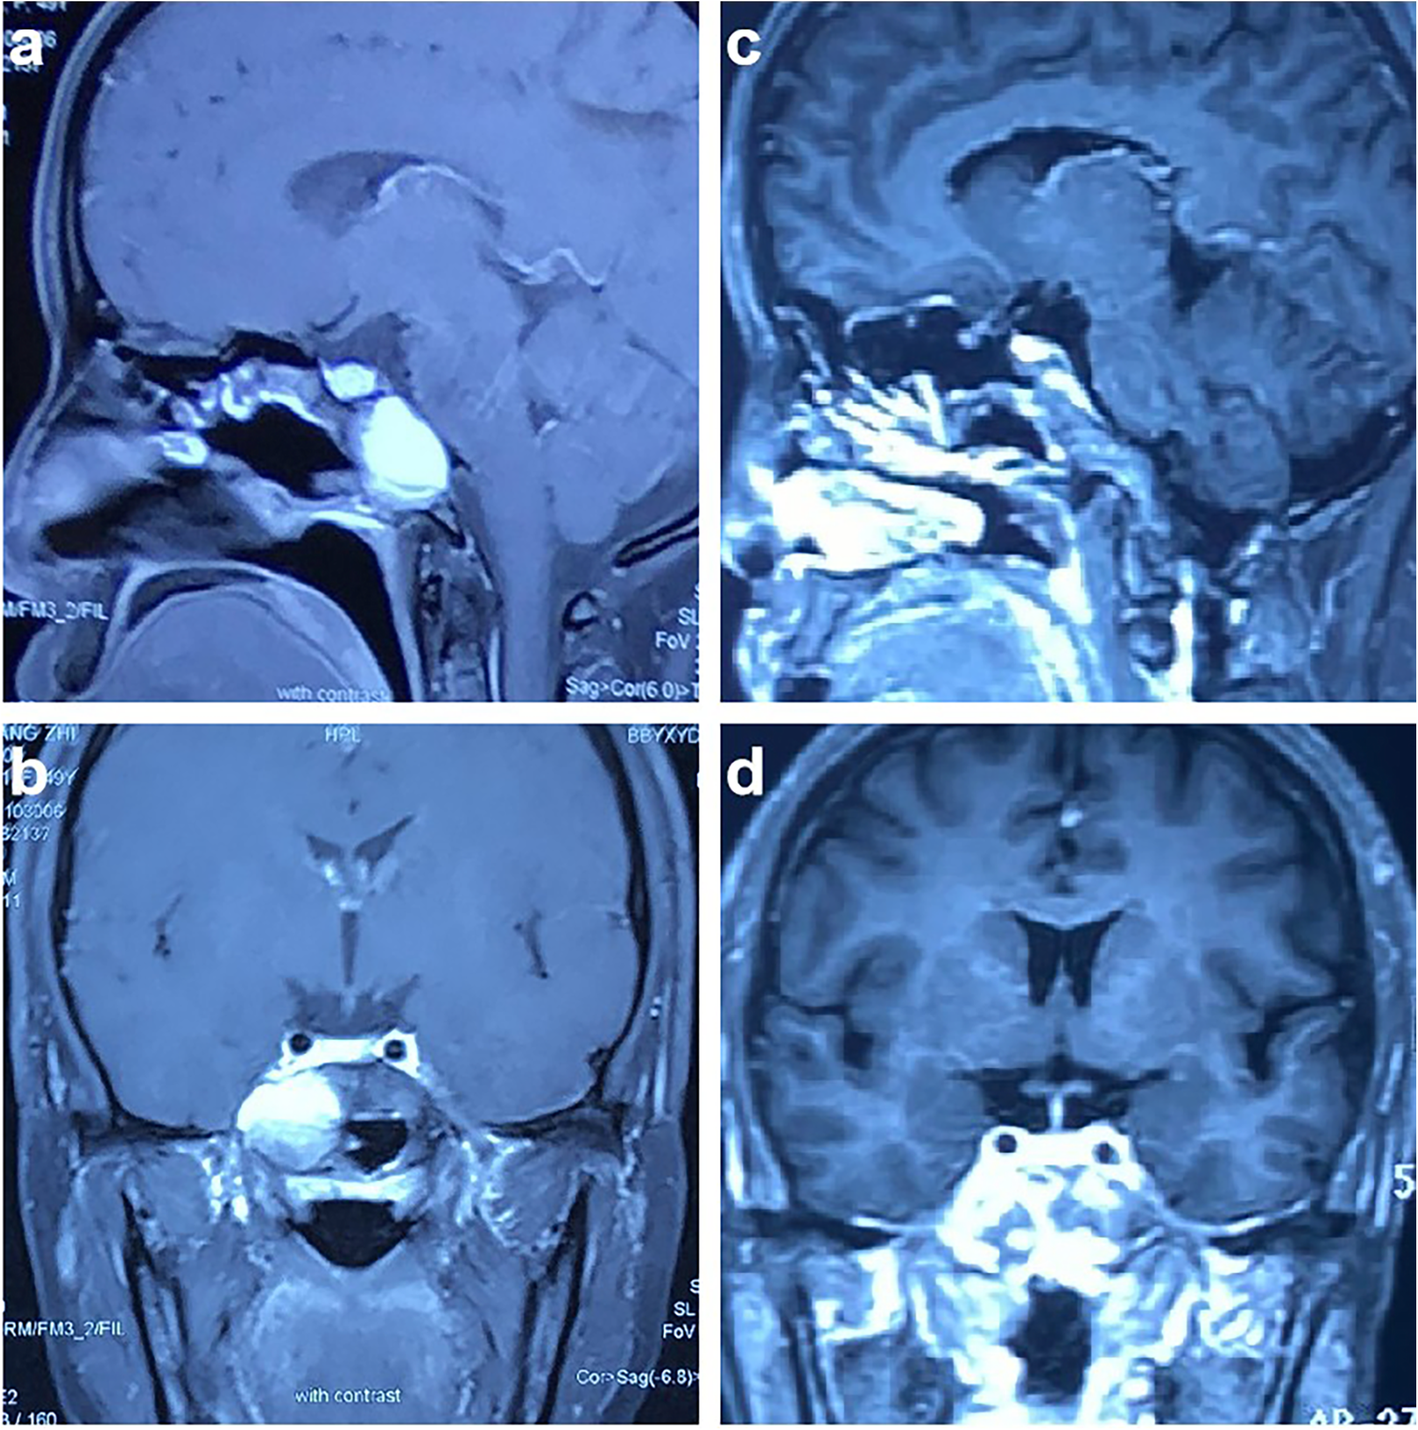

Fig. 1

From: Primary ectopic parasellar craniopharyngioma: a case report

Enhanced magnetic resonance imaging (MRI) of the patient’s head. Preoperative enhanced MRI, including sagittal (a) and coronal (b) views, showed uneven T1 hyperintensity. A lesion with a length of approximately 33 mm was identified in the sphenoid sinus and right parasellar region, but no obvious enhancement was found. Six months after surgery, sagittal (c) and coronal (d) contrast-enhanced T1 MRI showed no residual tumor near the sella and no local recurrence